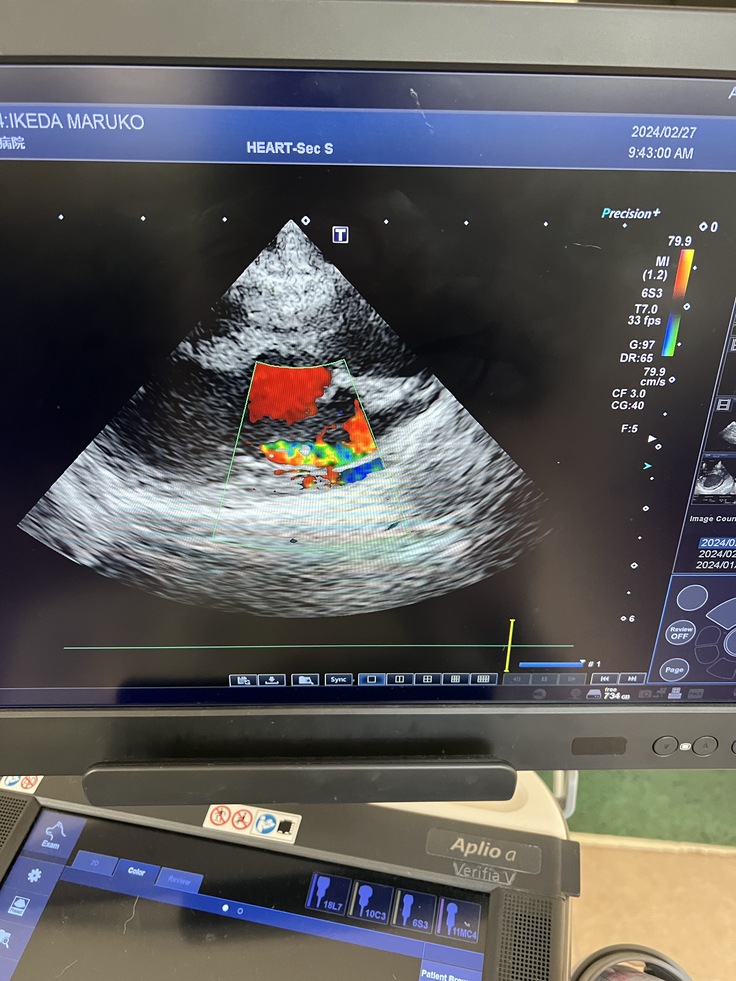

↑まる子のエコー